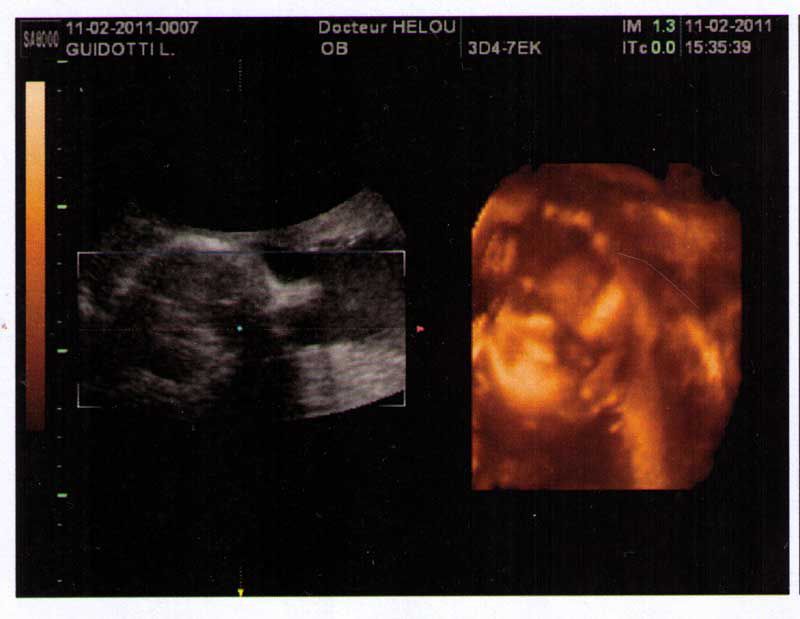

Par sellerieguidotti : le 11/02/11 à 19:33:10

| Dire merci | Bonjour les filles, ca fait un moment que je n'étais pas venue ! Bravo tagada, ton petit est vraiment choux ![]() Conny : j'ai eu ce problème de pertes vaginal, mon gygy dit que c'est normal que ça arrive, on secrète plus de je sais pas quoi. mais faire attention aux infections ![]() Sinon j'ai eu une écho aujourd'hui : Bébé pèse 905 grammes et mesure 30 cm ! tout va bien. Photo 3D de sa bouille écrasée sur le placenta ! il a cru que c'était un oreiller. Il a la tête en bas mais peut se retourné encore, et revenir a sa place tête en haut... bon, qu'il reste comme ça pas de soucis. ![]() Voilààà ![]() Ila la tête vers le bas. |